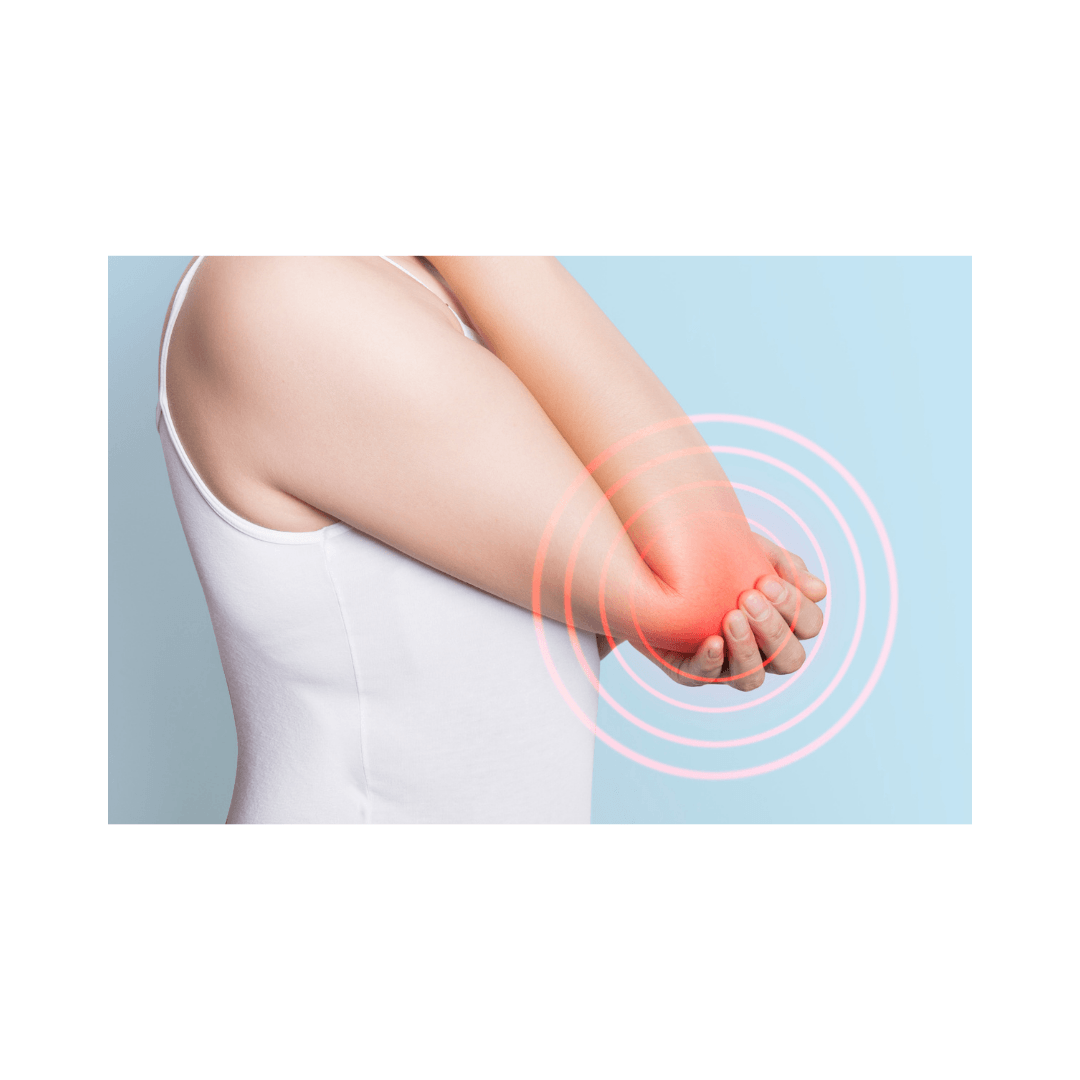

La inflamación está presente en todas las patologías, infecciones y lesiones y cumple con dos funciones imprescindibles para la supervivencia del nuestro organismo, la de ELIMINAR sustancias tóxicas, microorganismos patógenos, etc., y la de REPARAR tejidos dañados, por lo tanto, es imprescindible para la supervivencia de nuestro organismo y de el de la mayoría de seres vivos.

Los signos que caracterizan un proceso inflamatorio son el DOLOR, CALOR, RUBOR y TUMEFACCIÓN, la suma de todos ellos ocasiona impotencia funcional, es decir, dificultad para generar movimientos en los cuales se halle implicado el tejido inflamado.